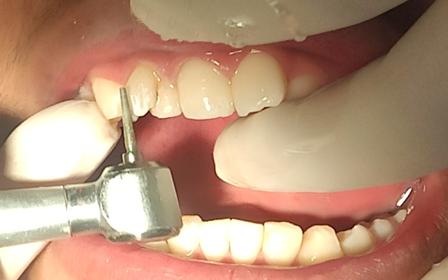

Al examen clínico intraoral se evidenció en la pieza, motivo de consulta, una alteración del desarrollo

dentario de forma, asemejando tener dos coronas en una sola pieza dentaria, unidas parcialmente en el tercio medio y cervical, delimitado por un surco central proveniente de la unión cementoesmalte, presentando una corona disto vestibular y otra mesiopalatina, hacia el borde incisal las coronas están separadas, también se evidencia a nivel del surco una caries de esmalte con cambio de coloración marrón (Fig. 1.A). A nivel de la cara palatina de la pieza 1.2 se evidencia la presencia de una cúspide accesoria en la corona mesiopalatina la misma que se denomina cúspide en garra (Fig. 1.B).

Figura Nº1 A. Fotografía intraoral en oclusión, señalando la pieza (1.2) note el surco vestibular con cambio de coloración. B. Fotografía intraoral oclusal se observa en la corona mesiopalatina la cúspide en garra.

Fuente: Elaboración propia, octubre 2021.